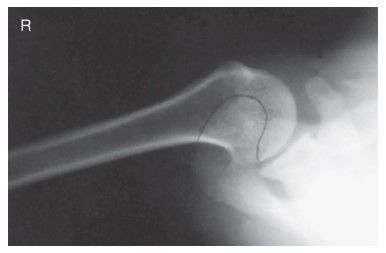

Which projection/position is this? PA Lateral Humerus